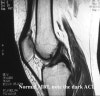

MRI는 전방십자인대 손상의 객관적인 진단 뿐 아니라 손상의 정도와 양상을 평가할 수 있고, 동반 손상을 진단하는데 매우 유용하여 치료방침 결정에 도움을 줄 수 있습니다.

MRI : 전방 십자인대 손상(ACL injury, ACL tear)